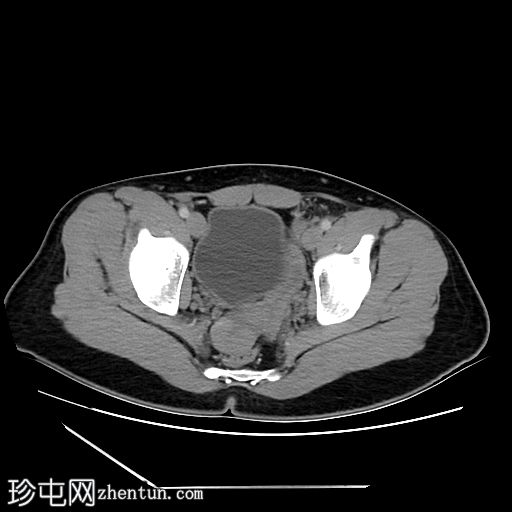

冠状位增强扫描

动脉期

4.jpg

盆腔左侧可见一形态良好的子宫样结构(57 x 17毫米),开口于前列腺尿道。

右侧睾丸位于盆腔右侧,膀胱与直肠之间。大小:56 x 29 毫米。

左侧睾丸位于盆腔中线左侧,膀胱上方,子宫底旁。该结构附着于从左侧腹股沟管延伸出的索状结构上。大小:38 x 22 毫米。

患者有双侧隐睾病史。CT和MRI图像显示发育良好的子宫和两个睾丸,均位于盆腔内。子宫内膜腔开口于前列腺尿道。